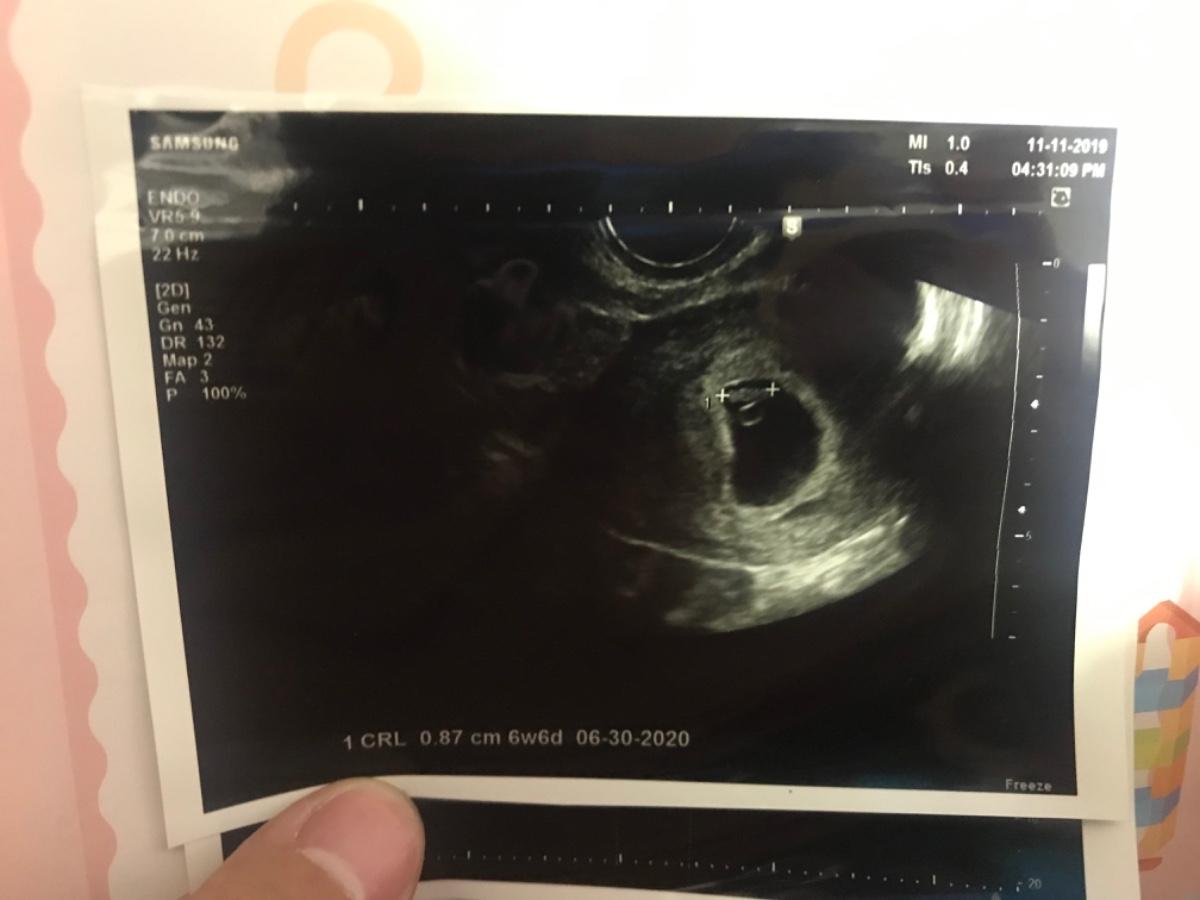

108/11/11~

自從10/28確定懷孕後,11/11應該算是我第一次產檢,這次世爺雖然有想辦法下午請假趕來婦產科陪我產檢,但是還是來不及😅~

#懷孕6週多